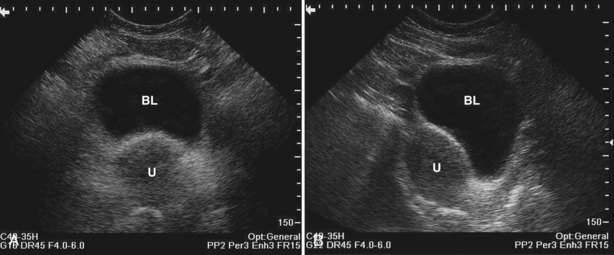

A voiding cystourethrogram (VCUG) is performed to evaluate the anatomy and physiology of the bladder and urethra. The study provides valuable information regarding the posterior urethra in pediatric patients. VCUG has long been used to demonstrate vesicoureteral reflux.

The study may be performed with the patient supine or in a semiupright position using a table capable of bringing the patient into the full upright position. A preliminary pelvic plain radiograph is obtained. In children a 5- to 8-Fr feeding tube is used to fill the bladder to the appropriate volume. Patient comfort should be taken into account when determining the appropriate volume. In the adult population a standard catheter may be placed and the bladder filled to 200 to 400 mL. The catheter is removed and a film is obtained. During voiding, AP and oblique films are obtained. The bladder neck and urethra may be evaluated by fluoroscopy during voiding. Bilateral oblique views may demonstrate low-grade reflux, which cannot be appreciated on the AP film. In addition, oblique films will demonstrate bladder or urethral diverticula, which are not always visible in the straight AP projection. Postvoiding films should be performed (Fig. 4–11).